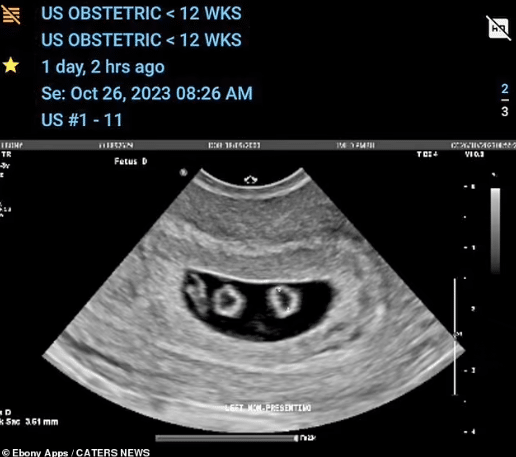

At first, they expected just one set of identical twins, but their world turned upside down during the second ultrasound on October 26.

“We went to our first ultrasound expecting just one baby, then we were told it was twins.

“Then at our second scan, we were told we were having quadruplets that were two sets of identical twins,’ Ebony said.

The attending doctor, breaking the news, revealed that they were not only expecting quadruplets but two sets of identical twins, which is rare even in multiple pregnancies.